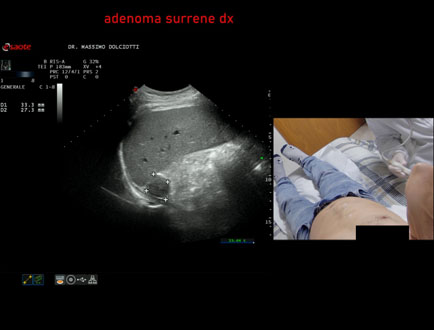

Data inserimento: 02/04/2021

Ecografia del: 01/04/2021

Strumento: Esaote MyLab Twice

Sonda: Convex Multifrequenza 1-8 MHz

Età Paziente: F 76 anni

Motivazione dell'esame: follow up di adenoma surrenalico destro.

Commento all'esame: le immagini ed il video documentano formazione ipoecogena, in sede surrenalica destra, delle dimensioni massime documentate di 33,1 x 21,5 mm, da ricondurre ad adenoma surrenalico.

Conclusioni: adenoma surrenalico destro (right adrenal adenoma).

Presentazione: Dr. Massimo Dolciotti - Ancona

Elaborazione digitale: Andrea Dini - Ancona